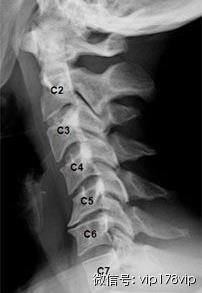

怎样才能知道自己的颈椎是否健康?日常生活中身体发出的小信号会提示不同类型的颈椎问题。

信号一:长时低头伏案工作,感觉到头晕难受,考虑为椎动脉型颈椎病;

信号二:不明原因的肩颈酸痛,手臂发麻,考虑为神经根型颈椎病;

信号三:正常直行走路却常出现“跑偏”问题,考虑为脊髓型颈椎病;

信号四:经常有不明原因的头晕、眼花、耳鸣、手麻、心动过速、心前区疼痛等一系列症状,考虑为交感神经型颈椎病。

如果同时出现上述几类症状,则考虑为混合型颈椎病。